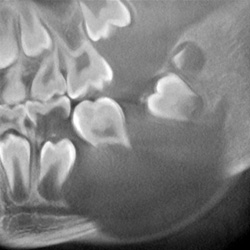

Kieferorthopädie

• Diagnostik von Anomalien des Zahnbestandes

• Diagnostik von Anomalien und Dysplasien der Zahnwurzel

• Differentialdiagnostische Bewertung von Zahndurchbruchstörungen

• Darstellung des peridentalen Knochenangebotes zur prognostischen Bewertung geplanter Zahnbewegungen

• Lageanomalien von Zähnen